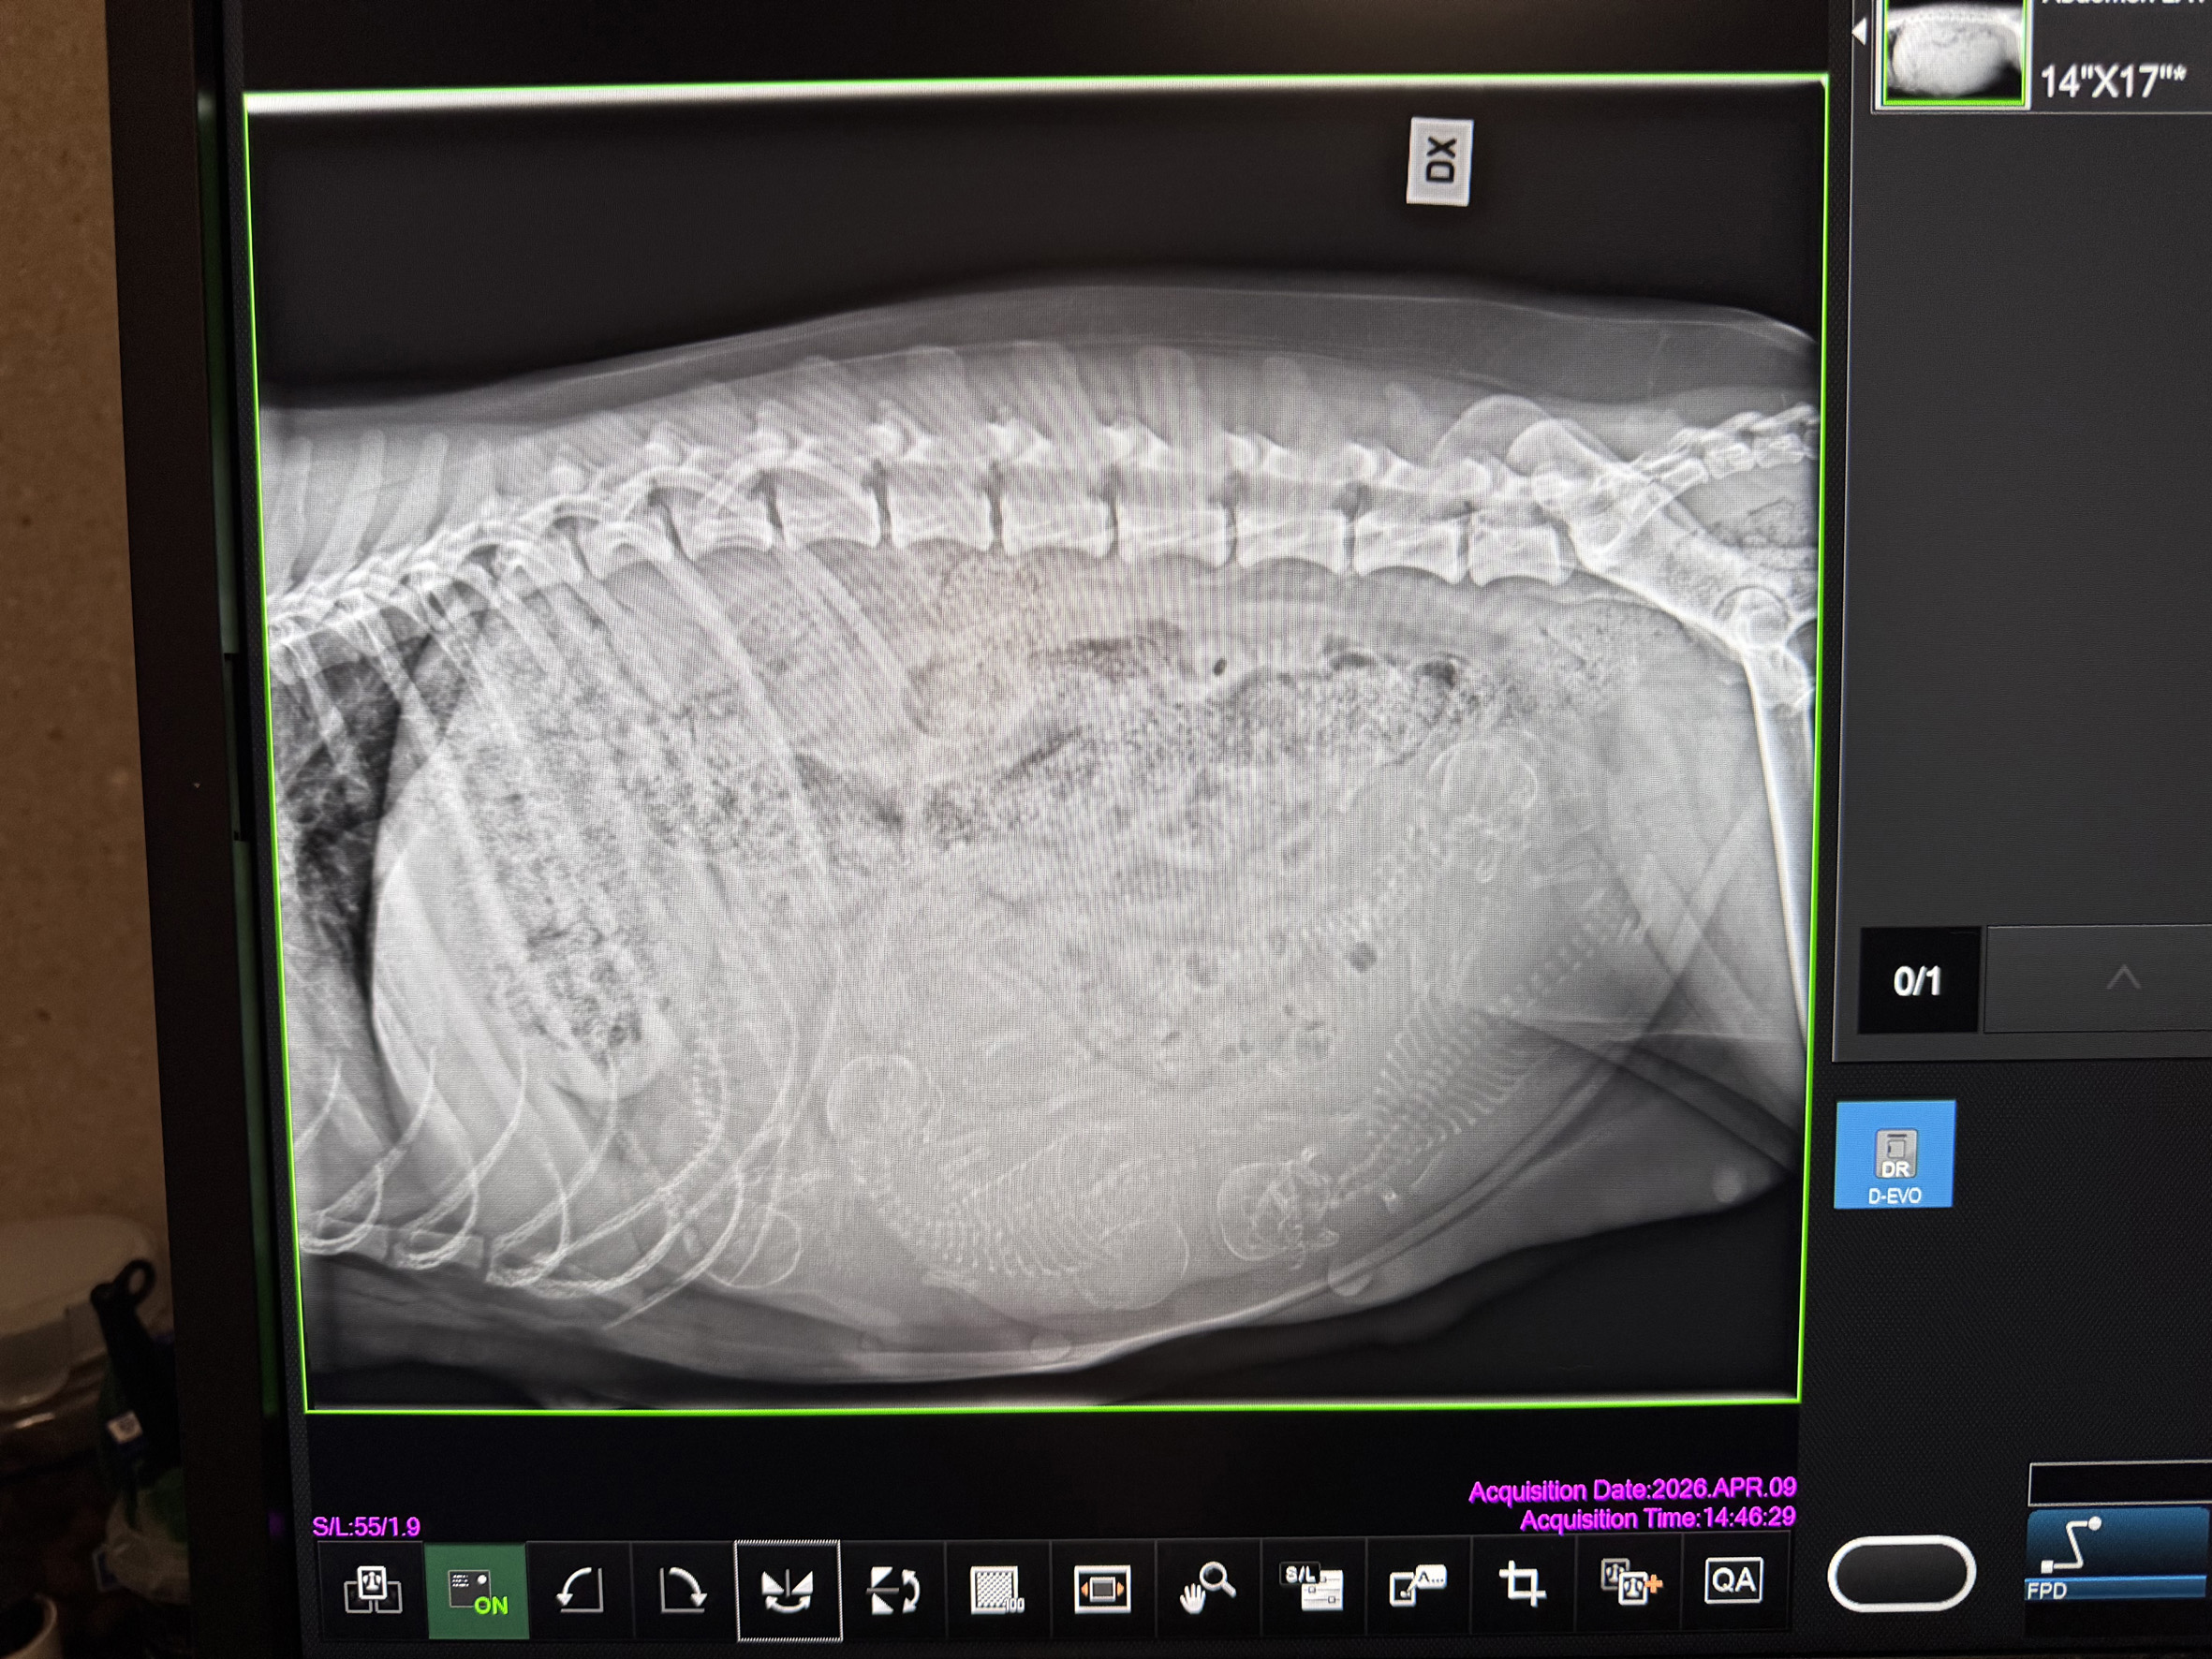

9 april 2026

Det visade sig att det blir 6 stycken valpar. En liten överraskning då en av valparna lyckades gömma sig vid ultraljudet som vi tog den 18 mars. Nu räknar vi ner dagarna – beräknad födsel är den 20 april ± 1 dag. Vi och våra valköpare ser nu fram emot att få träffa de små.

Holly är idag konstaterad dräktig med minst 5 valpar, till vår stora glädje. Veterinär Harriet Noring på Knallens Smådjursklinik i Borås gjorde idag ultraljud på Holly. Om 3 veckor är det dags för röntgen för att kunna se det exakt antalet valpar, vilket är bra att känna till när det är dags för Holly att föda.